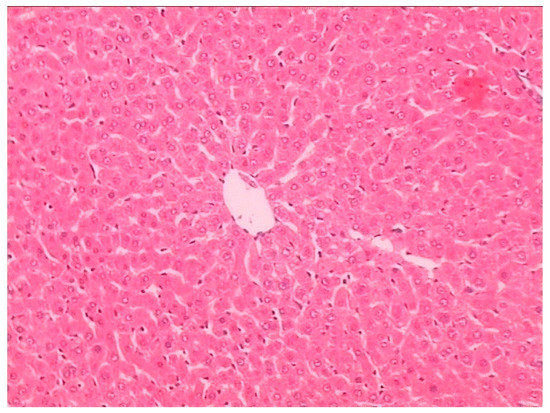

2.3. Histopathological Examination